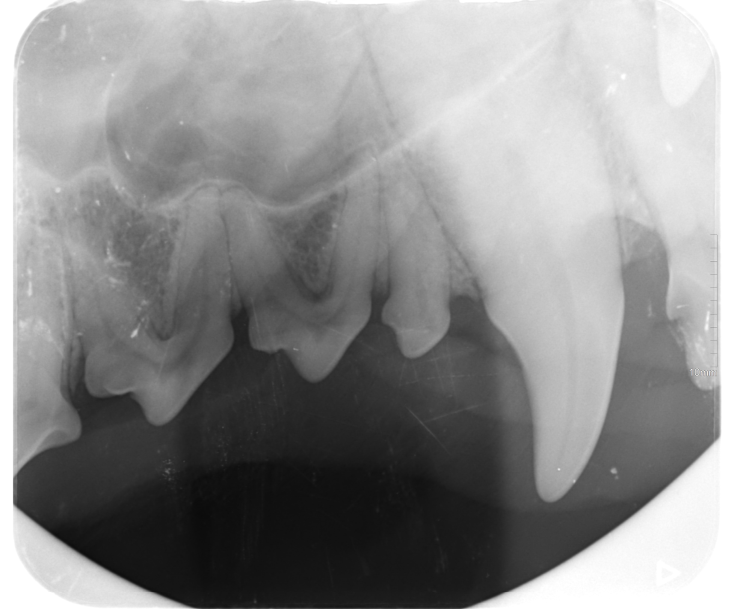

På Dyrlægen i Nærheden tilbydes tandrens af din hund og kat. Vi har mulighed for at lave tandrøntgen og tandekstraktioner i den fuldt udstyrede tandklinik.

Mange hunde og katte får tandproblemer og har behov for at få renset tænderne. Hvis der har været tandsten i længere tid, fører dette til tandkødsbetændelse, der kan udvikle sig til parodontose. Dette er en smertefuld tilstand, hvor tænderne bliver løse. Derfor er de dårlige tænder nødt til at blive opereret ud, så kæledyret kan få sin livskvalitet tilbage.

Mange hunde og katte har behov for tandrens 1-2 gange om året for at undgå parodontose.